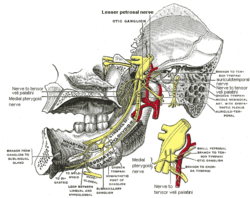

Mandibular division of trifacial nerve, seen from the middle line. Nerve to medial pterygoid labeled at bottom. | |

The nerve to the medial pterygoid muscle is a slender branch of the mandibular nerve which enters the deep surface of the muscle; it gives off one or two filaments to the otic ganglion.

The nerve provides physical support for the otic ganglion, but is neurologically distinct.